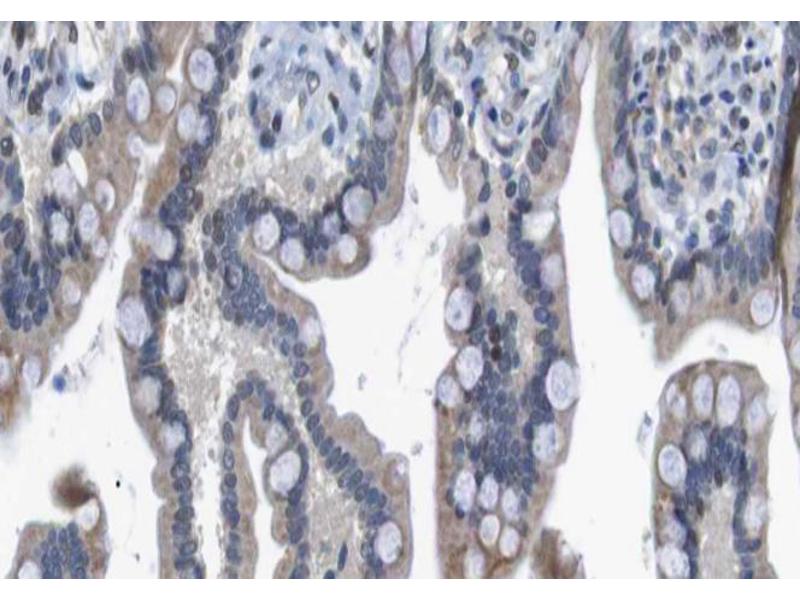

HDAC7 Reactivité: Humain, Souris WB, ELISA, IHC, IF, ICC Hôte: Lapin Polyclonal unconjugated

HDAC7 Reactivité: Humain, Souris, Rat WB, ELISA, IHC, IF, ICC Hôte: Lapin Polyclonal unconjugated